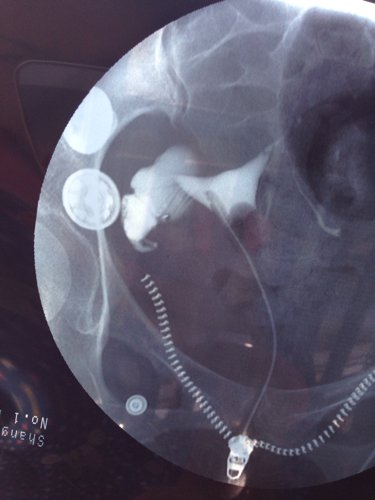

两年前做了宫外孕腹腔镜手术!最近做了输卵管造影!做腹腔镜那侧不通!另侧积水!我月经正常!应该怎样治

病情分析: 您好,根据您的描述是有输卵管堵塞的情况 指导意见: 您说的这种情况,是可以做一下腹腔镜输卵管整形造口术后,只要您排卵正常,术后3-6个月内怀孕的可能性还是较大的